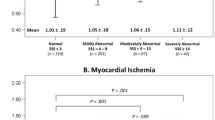

To demonstrate the relationship between CD and perfusion severity, visual and automated parameters were categorized to four severity groups (normal: normalized visual score (score = 0%) or STPD < 1%; mild: 1% ≤ normalized visual score or STPD < 3%; moderate: 3% ≤ normalized visual perfusion or STPD ≤ 10%; severe: normalized visual perfusion or STPD > 10%) based on clinical interpretation.

Stress perfusion variables in patients with or without CD on follow-up are presented in Table 1. Comparison of both groups shows that both visual and quantitative stress perfusion scores in patients with CD on follow-up were much larger than those without events (4.0 vs 1.5, and 7.4% vs 3.3%, both P < .001). Figure 1 shows that the CD event rate for these matched subjects increased with increasing SPECT perfusion parameters generated from either visual or automated analysis classified by previous description in “Materials and Methods” section. For either visual or automated perfusion variable, the rate of CD in patients with severely abnormal scans was significantly greater than that in patients with normal scans (P < .02). In general, the trend of CD event rates along categorized VSSS was similar to those along categorized STPD. Although more than half of the patients in the matched population were visually scored as 0 (N = 89), and a third of the total patients had normal perfusion defects from STPD scores (N = 58), the CD event rate in patients with VSSS = 0 was similar to that in the patients with STPD < 1%. Even with the clinical information and quantitative scores’ aids, the CD event rates in patients categorized by VSSS_C were similar to those categorized by VSSS or STPD (normal: 38%; mild: 54%; moderate: 50%; and severe: 79%).

Bar chart illustrating the cardiac death event rate by SPECT perfusion results. The numbers above each bar are the fractions of cases with cardiac death to the total number of cases in each perfusion category. From left to right, each group bar is cardiac death event rate for normal, mild, moderate, and severe perfusion, respectively